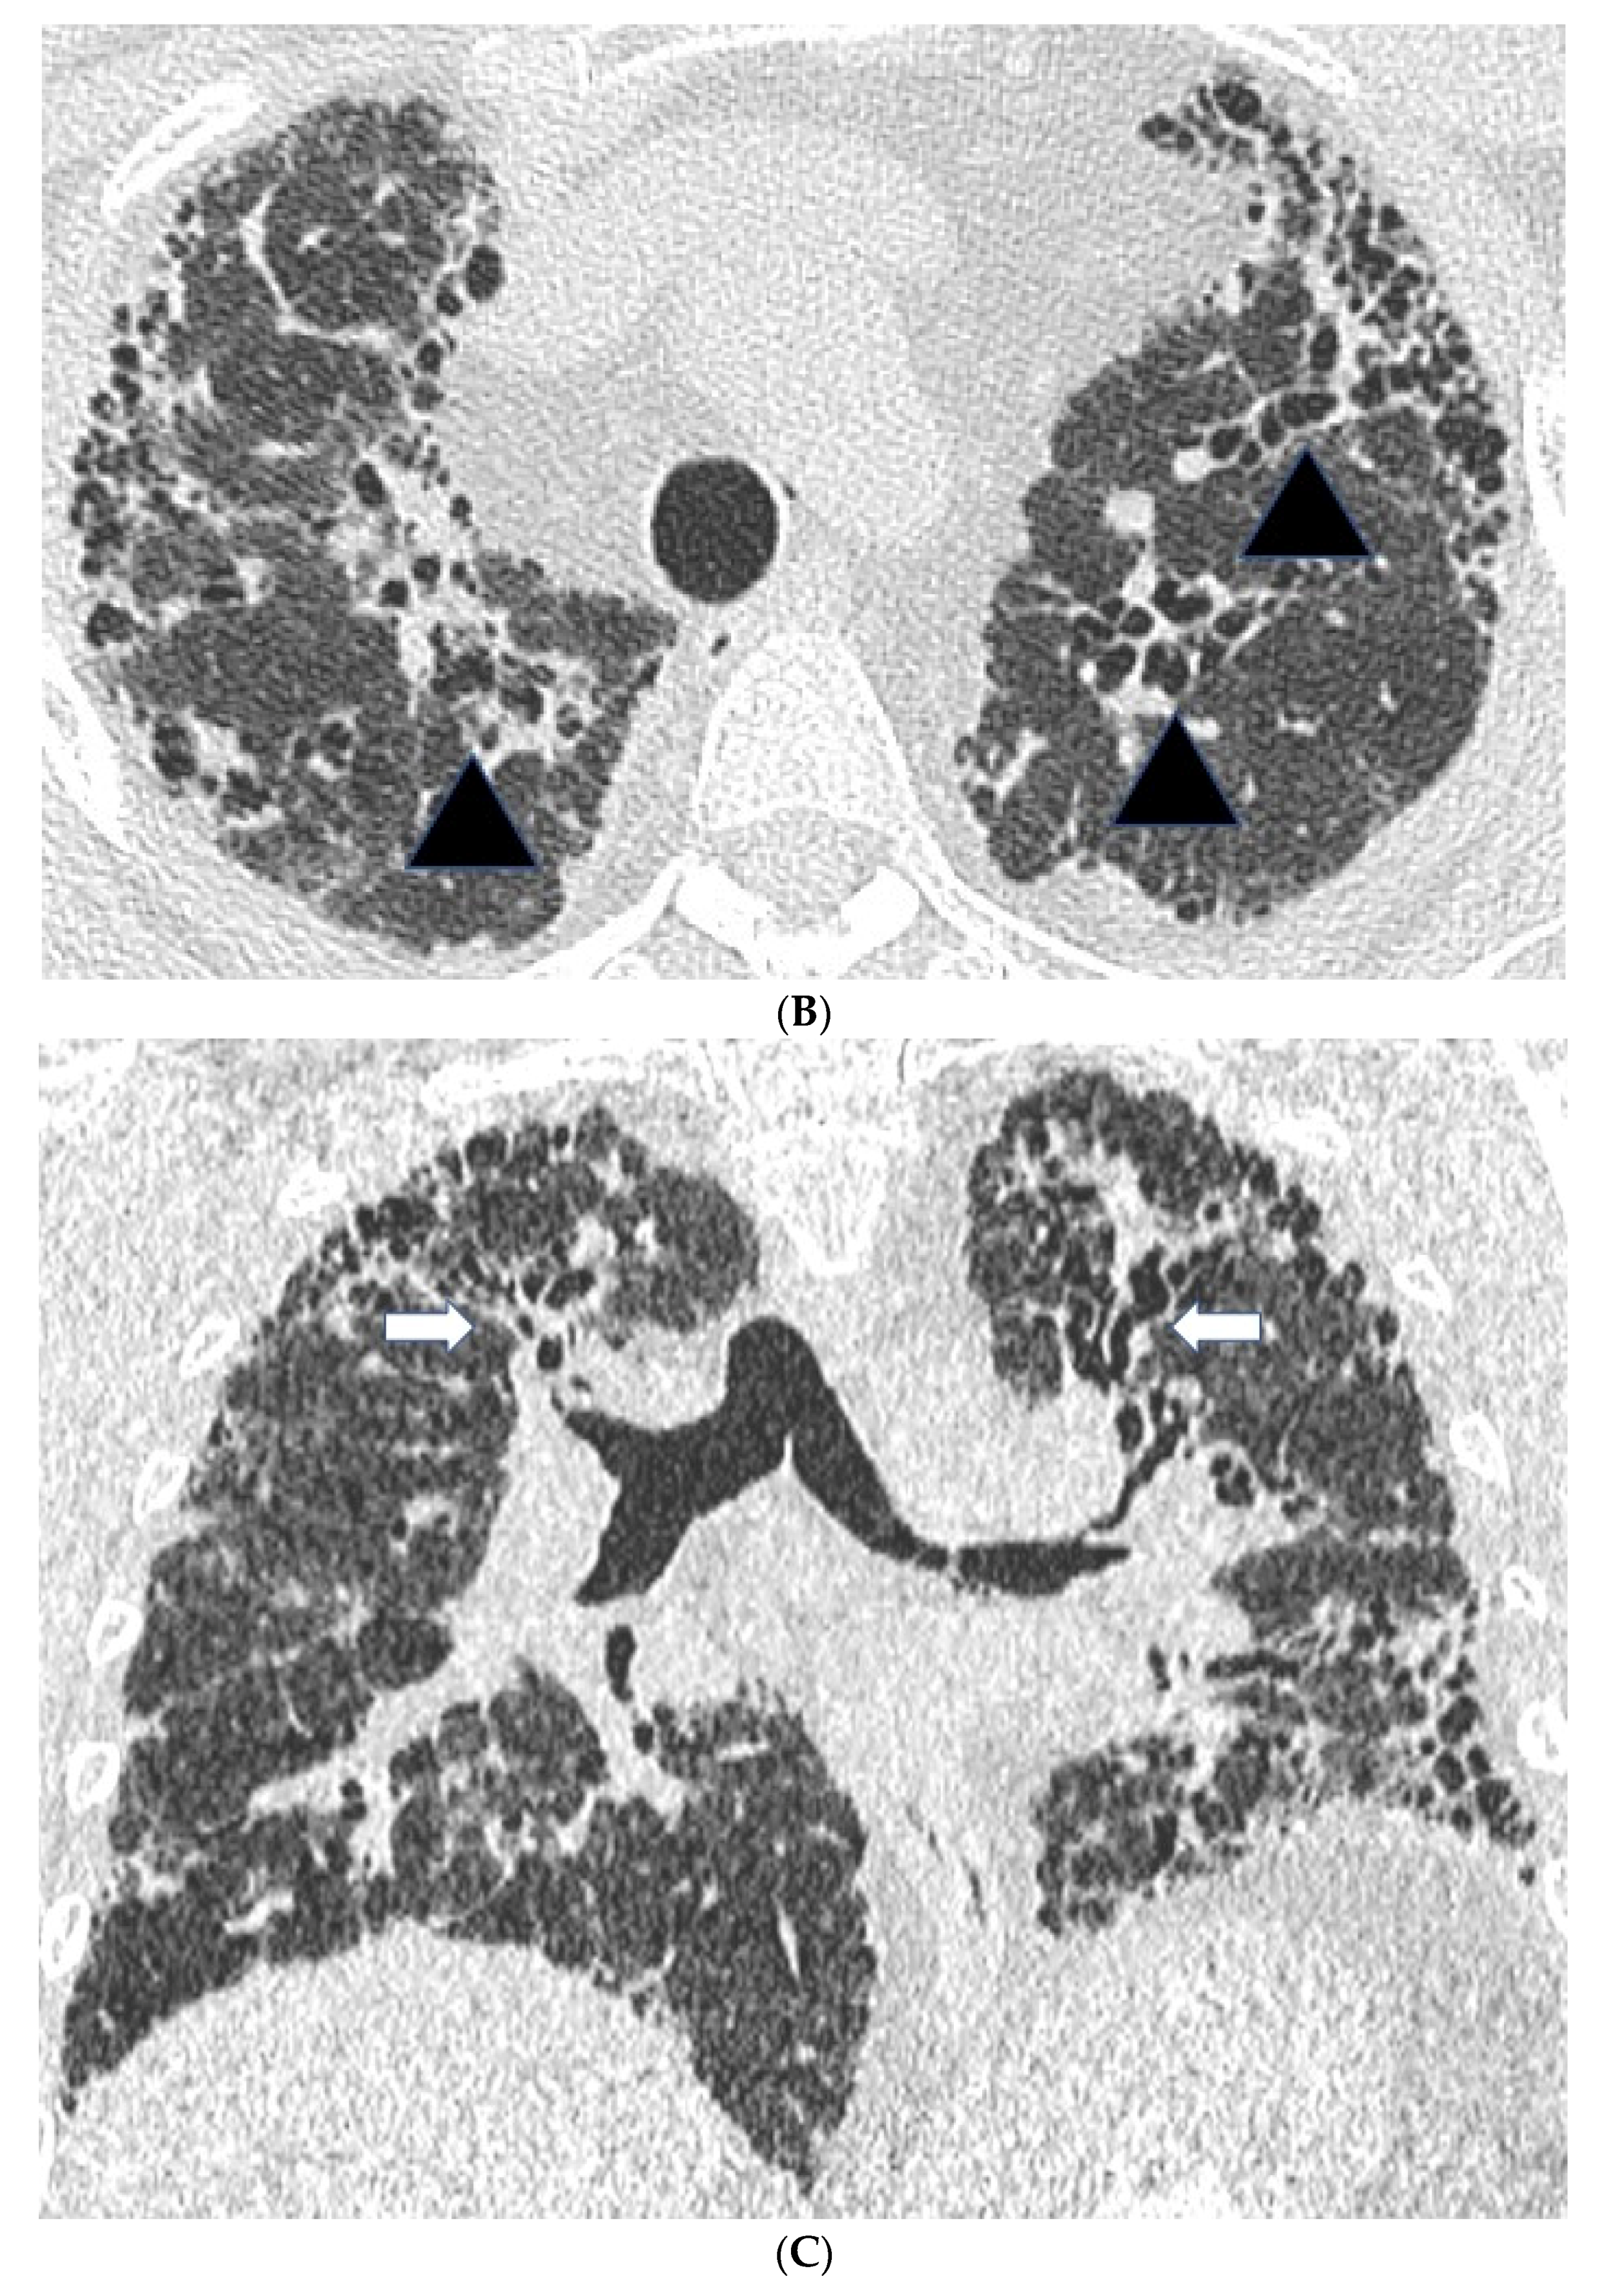

Figure 1. Features suggestive of chronic hypersensitivity pneumonitis in different patients. (A) Spared pulmonary lobules are visible within non-fibrotic lung bilaterally (arrows); background fibrosis is evidenced by peripheral reticulation and traction bronchiectasis (black arrowheads). (B,C) A predilection towards bronchocentricity of the fibrosis in the upper lobes is evident on axial (arrowheads) and coronal (arrows) images. (D) An upper and midzone predominance to the fibrosis, characterised by reticulation and traction bronchiectasis, is seen on a coronal CT. Incidentally, volume loss in the right lung is noticeable by slight tenting and elevation of the right hemidiaphragm (arrow). (E) A UIP pattern with honeycomb cysts is visible in the left midzone of the lung (arrowhead) in a 74-year-old male ex-smoker. A surgical biopsy performed a few years before this CT had demonstrated findings compatible with fibrotic hypersensitivity pneumonitis.

In fibrotic HP, CT patterns including reticulation, traction bronchiectasis and volume loss, with or without evidence of honeycombing, are all seen (Figure 1) [26,28]. Patients often demonstrate an upper lobe predominant distribution of fibrosis, but diffuse and lower lobe predominant changes have also been described. Furthermore, a faint bronchocentricity to the fibrosis can be observed at the lung apices. Similarly, reticulation in fibrotic HP is considered to have a predominantly subpleural or peri-bronchovascular distribution.

Mosaic attenuation with patchy areas of air trapping in a lobular distribution, more obvious on expiratory scans, is another important CT feature in HP. Lobular air trapping represents indirect evidence of small airways obstruction. (Figure 1A) However, mosaic attenuation can also be observed in other fibrotic lung diseases, including fibrotic sarcoidosis and connective tissue disease associated interstitial lung disease, also related to small airways involvement. As a result, lobular air trapping, which is often considered characteristic, may be a relatively non-specific finding. Interlobular septal thickening can be particularly profuse in fibrotic HP, although this is also a feature of fibrotic sarcoidosis. Consolidation is rare in HP and should raise the suspicion of alternative diagnoses such as fibrosing organizing pneumonia or sarcoidosis. Finally, cysts have been reported in 13% of patients with subacute HP but can also be seen in fibrotic HP [29]. The cysts are suspected to be a result of bronchiolar obstruction secondary to peribronchiolar lymphocytic inflammation, similar to that seen in lymphoid interstitial pneumonia.